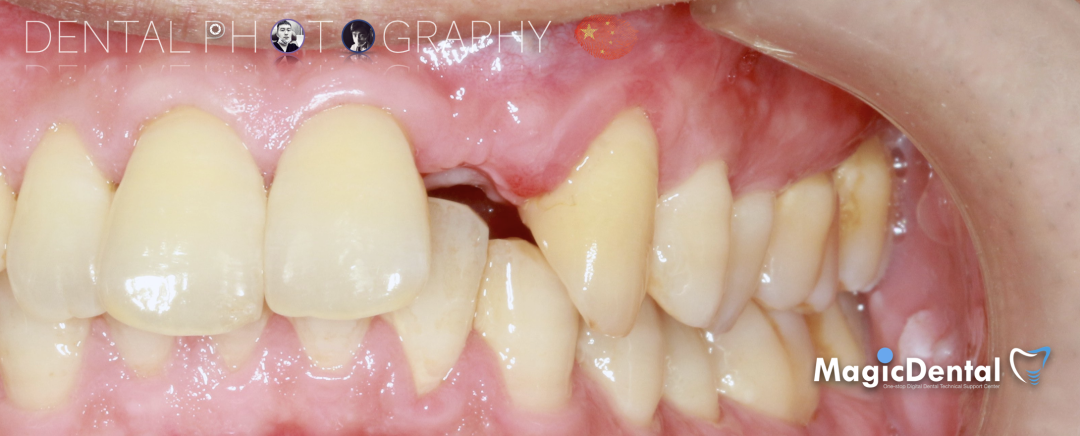

既往史:既往体健,无其他系统病史,否认重大疾病史,有口腔拔牙史。口腔检查:口腔卫生良好,牙周状况良好,22缺失,缺失间隙约7mm,CT显示缺失牙位置唇颚侧骨壁薄,无对颌伸长,邻牙无移位,上下前牙呈深覆 ,38、48近中阻生。

22缺失,且牙槽骨唇颚侧宽度较窄,38,48近中阻生。

治疗计划:水平骨增量,拔除四区近中阻生智齿,下颌升支外斜线处取块状骨,移植骨块至受区(22唇侧),种植修复22缺失牙。

切开翻瓣,彻底暴露术区,试戴骨块。

调整骨块外形,适配受植区域,打开骨髓腔。

预备固位钉洞,固定骨块

骨膜减张,放置骨粉,放置骨块,钛钉固定骨块。

固定骨片,修整骨块边缘,继续放置骨粉覆盖骨块及受植区,放置骨膜,严密缝合创口。